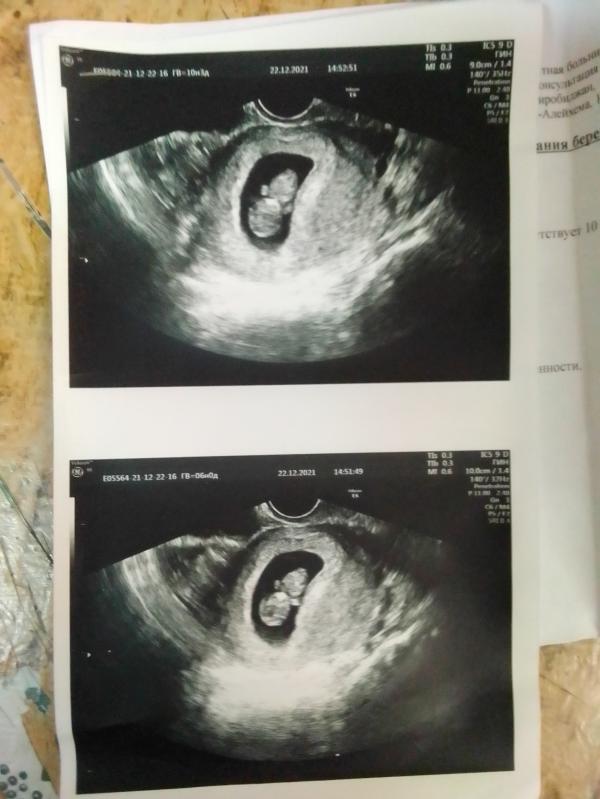

Наше первое узи, 9 неделя 3 дня, через 3 недели скрининг, очень сильно жду сына🥰💕